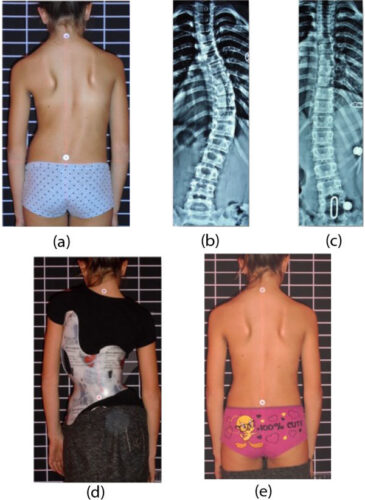

يعاني بعض المراهقين من اعوجاج العمود الفقري، وهو انحناء غير طبيعي للعمود الفقري قد يؤثر على المظهر الخارجي للجسم وثقة الطفل بنفسه. ومن أبرز طرق العلاج غير الجراحي الحزام الطبي، الذي يهدف إلى تثبيت العمود الفقري وتقليل الانحناء مع مرور الوقت. ومع ذلك، تعتمد فعالية الحزام بشكل كبير على دقة توزيع الضغوط داخله، إذ أن الطرق التقليدية غالبًا ما تعتمد على التقدير البصري والخبرة الطبية، مما قد يؤدي أحيانًا إلى نتائج أقل دقة. لذلك، ظهرت تقنيات حديثة تعتمد على المسح ثلاثي الأبعاد لتحسين تصميم الحزام وزيادة فعاليته.

أجرى الباحثون تجربة على ثمانية مراهقين يعانون من اعوجاج العمود الفقري، مقسمين إلى مجموعتين:

المجموعة الأولى: استخدمت الحزام التقليدي (C.B.) الذي يعتمد على تحديد الوسائد يدويًا.

المجموعة الثانية: استخدمت الحزام الجديد (N.B.) المصمم وفقًا لقياسات ثلاثية الأبعاد.

ثم تم متابعة جميع المرضى لمدة ثلاثة أشهر، مع تقييم عدة مؤشرات، منها:

زاوية كوب (Cobb Angle).

تماثل الجذع وشكل سطح الظهر.

مستوى رضا المريض عن الحزام.

شعور المراهق بتحسن مظهر جسمه.

كما لاحظ الباحثون الفرق في قبول المراهق للحزام وارتياحه أثناء الاستخدام، وهو عامل مهم لضمان الالتزام بالعلاج.